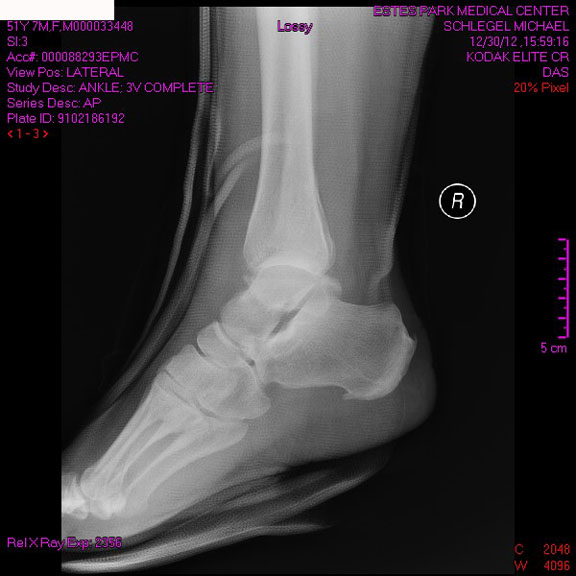

I made a stop at the Estes Park Medical Center, where they assessed me and took a few xrays, where it was immediately obvious that they couldn’t handle my trauma. I waited for transport down the mountain via a second ambulance and crew, and ended up finally at Good Samaritan Hospital in Lafayette, which has a huge emergency room. They began treatment quickly, taking off the hastily-places splint and taking more xrays, and by 11 p.m., my ankle had been minimally set and I was being admitted for the night pending surgery.

I broke my fibula in two places, one a near compound fracture, and broke the tip off the tibia, and dislocated the tibia. For a simple fall, this had very complex results. By the time they could set my ankle, it had been more than six hours since my break, and they were not confident that the “reduction” was going to work. If it didn’t, I would have needed immediate surgery, with followup surgery later. It did work, although there was intense swelling and fracture blisters (don’t look these up on google if you are squeamish). I spent 14 hours laying on my back in my hospital room, my head down and my ankle up high, trying to reduce the swelling for the surgery. It must have worked, as I went into surgery in good shape and came out in very little pain. I have at least one plate and a dozen screws holding the whole thing together. I’m padded and casted.

I have six weeks or more of healing in a cast in a non-weight-bearing status before I can start physical therapy. I will know more in a couple weeks when my stitches come out and I get a new, smaller cast. I’m including pictures of my xrays below, which are not particularly “ew”-inducing but give you an idea of what happened inside there. I am, at this point, feeling very very lucky, and have full faith that I will be healing up nicely. It just will take some time.

From the side, I don’t look so bad.